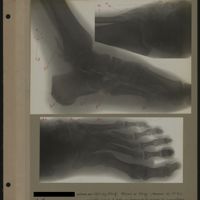

0097 - Page 93 - [Radiographies de la cheville et du pied]0097 - Page 93 - [Radiographies de la cheville et du pied]